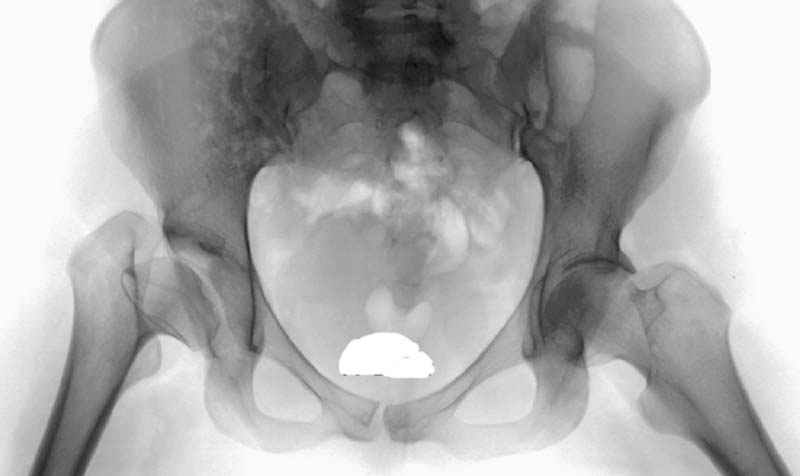

Рис.2 Та же трехмерная модель тазобедренного сустава без аналога связки головки бедра. Пружина динамометра удерживает тазовую часть модели от опрокидывания, поддерживая стабильность так же, как отводящие мышцы обеспечивают ее в отсутствии связки головки бедра.

Модель несовершенна, согласен, однако я экспериментировал и с импровизированной илеофеморальной связкой и ацетабулярной губой. Результат был тот же, подвижный узел замыкался посредством аналога СГБ. Для интереса я прилагаю фото., где сымитированы наружные связки и вертлужная губа, но без СГБ видно по показаниям динамометра, что данные структуры незначительно только на 0.5 кг разгружают аналог отводящих мышц. Почему модель получилась именно такой можно рассказать и подробнее если захотите…